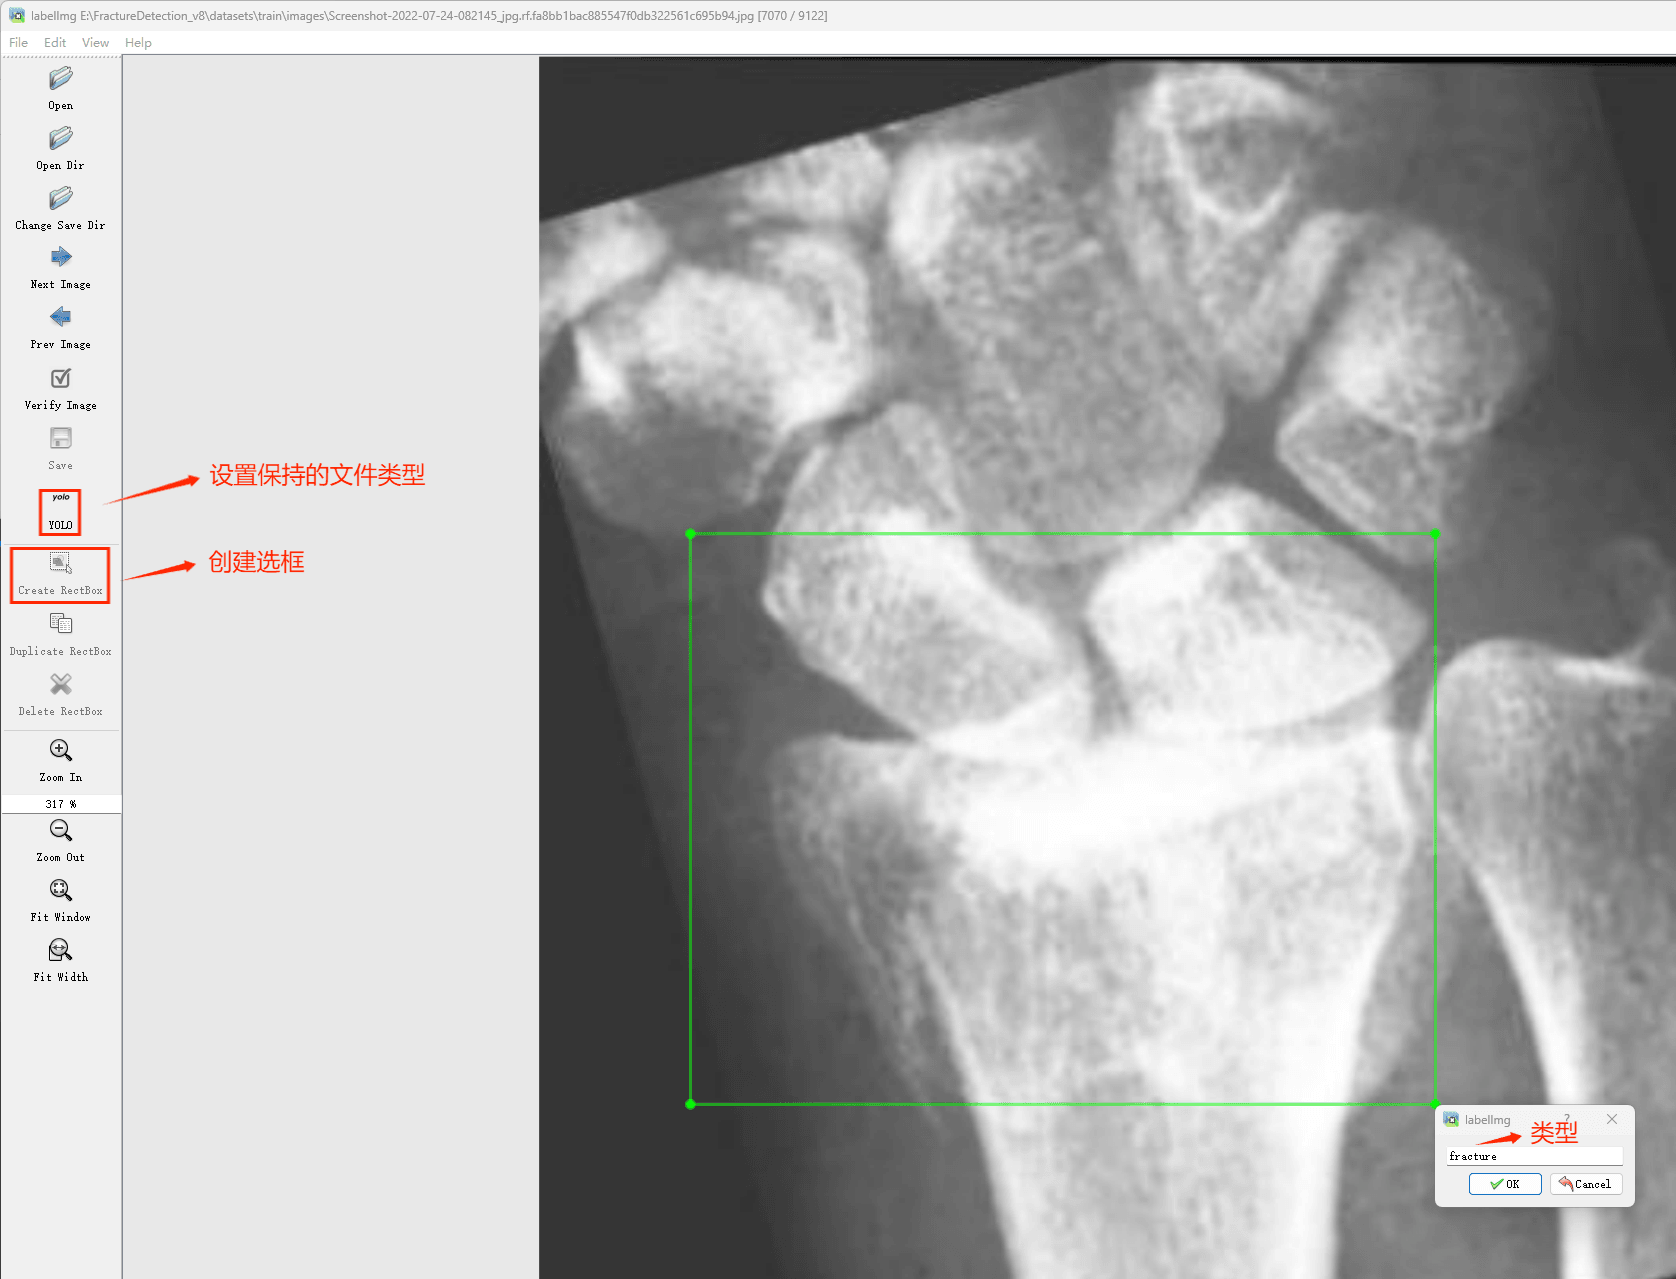

(4)YOLO模式创建标签的样式

存放标签信息的文件的文件名为与图片名相同,内容由N行5列数据组成。

每一行代表标注的一个目标,通常包括五个数据,从左到右依次为:类别id、x_center、y_center、width、height。

其中:

–x类别id代表标注目标的类别;

–x_center和y_center代表标注框的相对中心坐标;

–xwidth和height代表标注框的相对宽和高。

注意:这里的中心点坐标、宽和高都是相对数据!!!

存放标签类别的文件的文件名为classes.txt (固定不变),用于存放创建的标签类别。